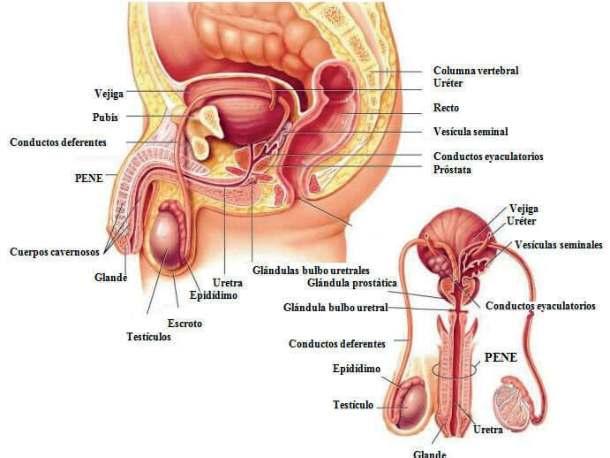

ASPECTOS BIOLOGICOS DE LA REPRODUCCIÓN HUMANA

Desde el nacimiento del ser humano claramente definidos sus organos sexuales (caracteres sexuales primarios). Con el trascurso de los años, al llegar a la pubertad el hipotálamo atúa sobre glándula hipófisis dando lugar a que las hormonas actúen tanto en los testículos en el caso de los hombre y los ovarios en caso de las mujeres llevando acabo la produccuón de espermatozoides y de hormonas. Su función se haxe evi dente durante el coito o la masturba ción, en los cuales representan variaciones en tamaño y posición de acuerdo a los niveles de exi tación.

ANATOMÍA GENITAL MASCULINA

Durante la excitación sexual los espermatozoides salen del epidídimo a través del conducto deferente. Allí se mezclan con el líquido producido en las vesículas seminales y la próstata para formar el semen.

Hay que destacar que el semen ayuda a nutrir a los espermatozoides y a la vez ha transportarlos

* La uretra: Esta transporta orina y semen. Durante el orgasmo el semen se eyacula por la uretra.

* Los testiculos: Son glándulas que producen espermatozoides y a la vez producen hormonas son células reproductoras.

* El epididimo: Este es un conducto enrollado que alberga a los espermatozoides mientras maduran.

* El conducto deferente: Transporta el esperma desde el epidídimo hasta el pene.